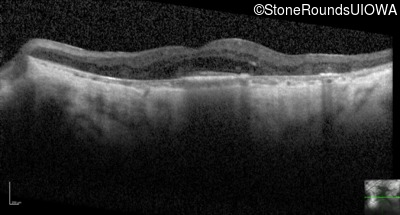

Optical Coherence Tomography - Left - 20/80

Exemplar / OCT Stack